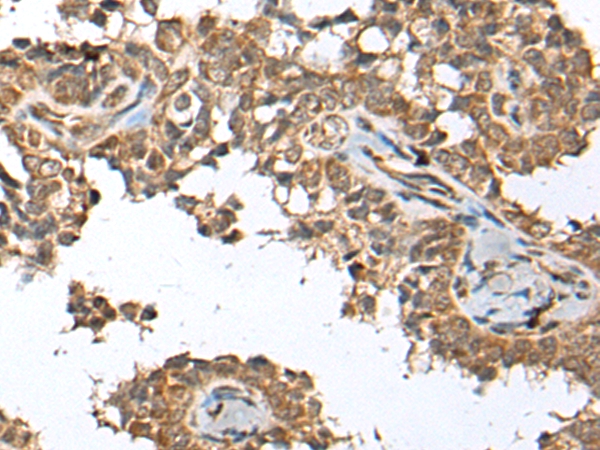

IHC (Immunohistochemistry)

(The image on the left is immunohistochemistry of paraffin-embedded Human thyroid cancer tissue using 46677(SPRTN Antibody) at dilution 1/65, on the right is treated with fusion protein. (Original magnification: x200))